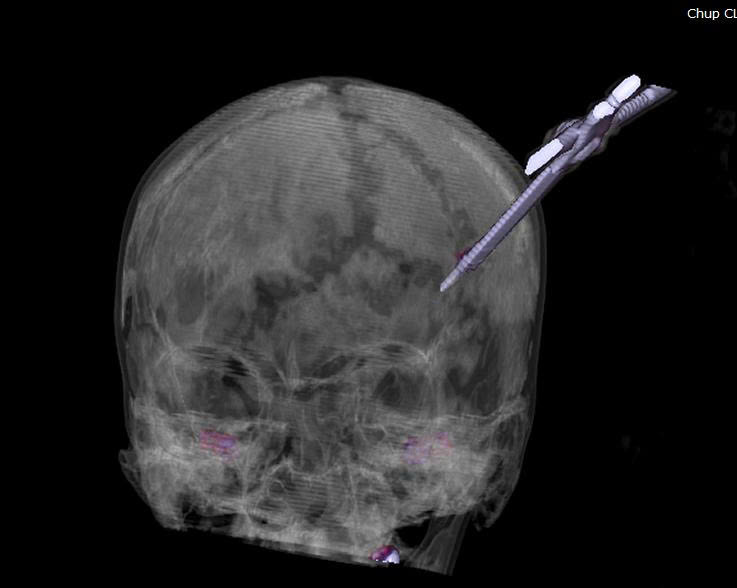

23/06/2025 23:07Kinh hãi cô gái 25 tuổi ở Quảng Ninh nhập viện với chiếc kéo sắc nhọn đâm xuyên sọ não

Mới đây, theo thông tin từ Bệnh viện đa khoa Quảng Ninh cho biết, tối ngày 20/6 đã tiếp nhận một trường hợp bệnh nhân N.T.H.N (25 tuổi) trú tại phường Giếng Đáy, nhập viện trong tình trạng tỉnh, vết thương vùng thái dương trái sưng nề do bị lưỡi kéo găm sâu vùng đầu.

Nhận định đây là một ca chấn thương sọ não phức tạp, người bệnh được chụp cắt lớp vi tính sọ não để đánh giá chính xác vị trí tổn thương và mức độ đâm xuyên của dị vật, từ đó có đường mổ an toàn, hạn chế tổn thương tối đa tổn thương não, tránh biến chứng nặng.

Dưới sự chỉ đạo trực tiếp của Bs.CKII Nguyễn Tiến Dũng, Phó Giám đốc Bệnh viện, kíp mổ hội chẩn với các chuyên khoa đánh giá đây là vết thương xuyên sọ sâu khoảng 5 cm xâm lấn nhu mô não, nguy cơ chảy máu sâu bên trong não kèm nguy cơ nhiễm trùng lan rộng do dị vật găm xuyên sọ, vì vậy bệnh nhân lập tức được chuyển phòng mổ cấp cứu lấy dị vật, xử trí tổn thương não cho người bệnh.

Ngay trong tối cùng ngày, kíp mổ cấp cứu khoa Phẫu thuật Thần kinh – Cột sống phối hợp với khoa Gây mê Hồi sức thực hiện. Qua phim chụp, các bác sĩ đánh giá dị vật không xâm lấn vào mạch máu lớn. Phẫu thuật viên tiến hành mở rộng xương sọ quanh vùng tổn thương và khéo léo lấy dị vật ra khỏi hộp sọ. Sau khi loại bỏ tác nhân gây tai nạn, kíp mổ tiếp tục làm sạch vết thương, cầm máu triệt để và tạo hình lại vị trí màng não bị rách, đụng dập do dị vật gây tổn thương.

Sau 1 giờ phẫu thuật, ca mổ đã được thực hiện an toàn và thành thành công. Hiện tại, các chỉ số sinh tồn của bệnh nhân ổn định, đã tỉnh táo và vận động tốt

Ths.Bs Trần Bá Tuấn, khoa Phẫu thuật Thần kinh – Cột sống, Bệnh viện Đa khoa tỉnh, cho biết: “Trường hợp của bệnh nhân N. là ca chấn thương sọ não nguy hiểm, phức tạp với lưỡi kéo sắc nhọn găm sâu và chặt vào trong não. Nếu không kiểm soát tốt tổn thương khi rút dị vật nguy cơ chảy máu ồ ạt khó cầm.

Sau ca phẫu thuật, bệnh nhân đã tỉnh táo, vận động bình thường nhưng vẫn cần được theo dõi sát để phát hiện kịp thời các biến chứng như phù não, nhiễm trùng hay tổn thương thần kinh thứ phát”.

Các bác sĩ khuyến cáo người dân khi không may bị dị vật đâm sâu vào cơ thể, tuyệt đối không nên cố rút dị vật ra. Điều quan trọng là ngay lập tức sơ cứu, cố định dị vật và đưa bệnh nhân tới cơ sở y tế có chuyên khoa thần kinh để xử trí kịp thời.

Bởi trong các trường hợp tai nạn, dị vật có thể đóng vai trò như một nút cầm máu tạm thời, nếu vội vã rút ra, bệnh nhân có thể tử vong vì chảy máu ồ ạt. Ngoài ra, rút dị vật không đúng còn làm tổn thương mạch máu, thần kinh nặng nề, gây khó khăn cho bác sĩ phẫu thuật. Việc rút dị vật chỉ được thực hiện trong phòng mổ vô khuẩn bởi các bác sĩ có kinh nghiệm trong phẫu thuật thần kinh.